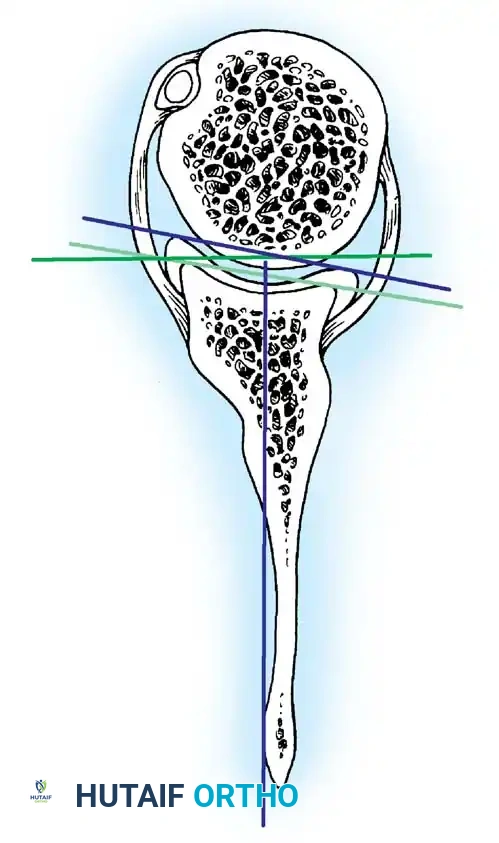

An exhaustive comprehension of normal functional anatomy is the cornerstone of diagnosing and surgically correcting shoulder instability. The bony architecture of the glenohumeral joint provides minimal inherent stability. The glenoid fossa is a flattened, dish-like structure, often compared to a golf tee. At any given time, only one-fourth to one-third of the large humeral head articulates with the glenoid. Unlike the deep acetabulum of the hip, this small, flat glenoid relies heavily on soft-tissue augmentations.

The Glenoid Labrum and Biceps Anchor

According to seminal studies by Howell et al., the effective depth of the glenoid is increased by 50% due to the presence of the fibrocartilaginous glenoid labrum. This structure acts as a bumper, increasing the humeral contact area to 75%. Integral to the superior glenoid labrum is the insertion of the long head of the biceps tendon, which blends indistinguishably into the posterior and anterior superior labrum. Matsen et al. conceptualized the labrum as a "chock block" that prevents excessive humeral head translation and rollback during physiological loading.

The shoulder joint capsule is inherently lax and thin, offering little resistance in isolation. However, it is reinforced anteriorly by three distinct capsular thickenings—the glenohumeral ligaments—which fuse intimately with the labral attachment on the glenoid rim. Turkel et al., alongside O’Brien, Warren, and Schwartz, have extensively mapped these structures.

- Superior Glenohumeral Ligament (SGHL): Attaches to the superior glenoid tubercle near the apex of the labrum, conjoined with the biceps anchor. It inserts onto the anterior aspect of the anatomical neck of the humerus. The SGHL is the primary restraint to inferior humeral subluxation at 0 degrees of abduction and serves as a primary stabilizer against anterior and posterior stress in the adducted arm. Harryman et al. demonstrated that tightening the rotator interval (which encompasses the SGHL and coracohumeral ligament) significantly decreases posterior and inferior translation.

- Middle Glenohumeral Ligament (MGHL): Features a wide origin extending from the SGHL along the anterior glenoid margin down to the junction of the middle and inferior thirds of the rim. It limits external rotation when the arm is in lower and middle ranges of abduction (45 degrees) but becomes redundant at 90 degrees of abduction.

- Inferior Glenohumeral Ligament (IGHL) Complex: The most critical static stabilizer. It attaches to the glenoid margin from the 2-o’clock to 3-o’clock positions anteriorly, extending to the 8-o’clock to 9-o’clock positions posteriorly. Its humeral attachment lies below the articular margin on the anatomical and surgical neck. O’Brien et al. described this complex as a "hammock-like" structure consisting of a thickened anterior band, a posterior band, and a thinner axillary pouch.

CLINICAL PEARL: The biomechanics of the IGHL complex are dynamic. With external rotation and abduction, the hammock shifts anteriorly and superiorly; the anterior band tightens to prevent anterior translation, while the posterior band fans out. Conversely, internal rotation tightens the posterior band. The anteroinferior band is the primary restraint to anterior translation at 90 degrees of abduction and external rotation (the classic apprehension position).